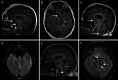

Intracranial Hypotension With Mild Parkinsonism and Bulbar Dysfunction